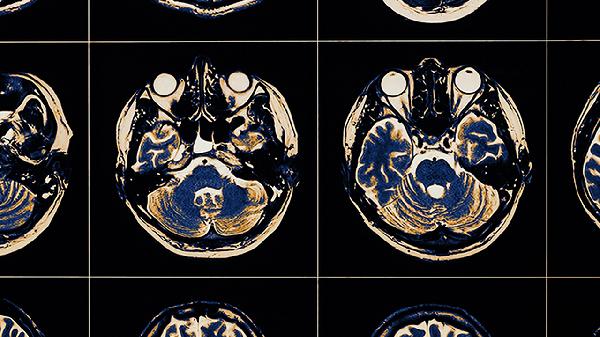

脑血栓片属于处方药,须严格遵医嘱使用。服药期间应保持低盐低脂饮食,适度进行肢体康复训练,控制血压血糖在正常范围。建议每3-6个月复查颅脑CT或MRI评估治疗效果,出现新的神经功能缺损症状应立即就诊。